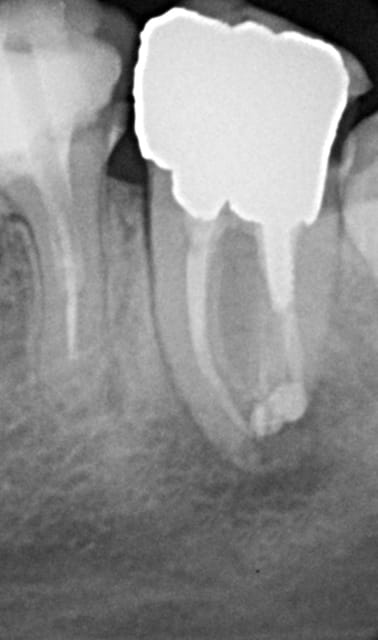

encore des radios,peut-etre assez moyen comme traitement...mais je vu pire...

les dernieres radios. patient en urgence ,abces... il voulait pas extraire la dent. j'ai lui bien explque et il a choisi de essayer de garder la dent. retrait,pas d'isolation avec la digue donc pas de tenon fibree,amalgam et screw post.traitement fait il ya 2 ans je crois.patient fidel de cabinet maintenent.